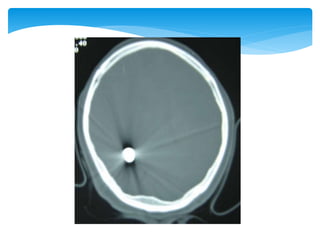

 Appearance of the normal structures

CT Scan

 Appearance ofthe normal structures CT Scan